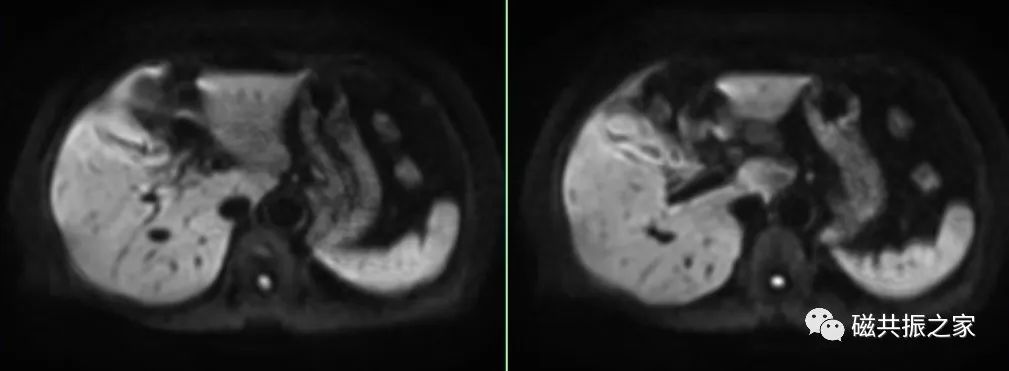

横轴面:横轴面DWI序列

复制横轴面T2WI序列的定位线

为了兼顾信噪比和病灶检出率,应合理使用b值的大小,1.5T b值建议600-800,3.0T b值建议800-1000,甚至更高。